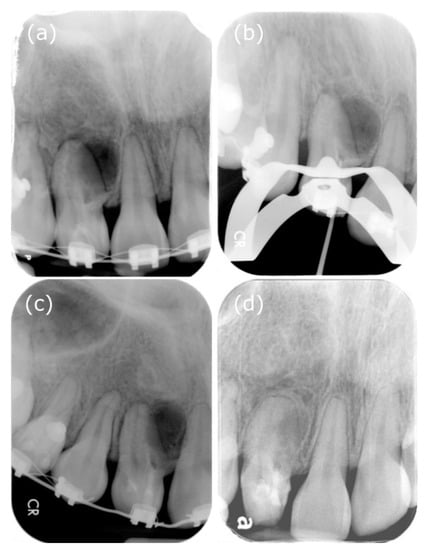

We decided to investigate further with CBCT because of the complex anatomy of tooth 12. As expected, the CBCT scan (EPX-Impla; E-Woo Technology, Yongin, Korea) revealed a type III invagination. We can observe from the CBCT coronal view that the pseudo canal was located near the buccal part, while the CBCT sagittal view showed that the buccal side of the pseudo canal with the opening of the invagination near the cemento-enamel junction, and it was adjacent with a well-defined unilocular peri-invagination radiolucent lesion measuring 8 mm (mesiodistal) × 9 mm (labiopalatal) × 12 mm (craniocaudal) (Figure 3). Three-dimensional CBCT aided the diagnosis and provided additional information on the root canal during the treatment procedure. A diagnosis of Oehler’s type III DI with necrotic invagination and asymptomatic peri-invagination periodontitis was made. We decided to proceed with the vital pulp therapy of the main canal, followed by nonsurgical endodontic treatment for the pseudo root canal, after discussing the treatment plans with the patient.

Figure 3.

Different sections in cone-beam computed tomography. (a) From the axial view, “pseudo-canal” can be observed on the mesial side, surrounded by the enamel. (b) The opening of the invagination near CDJ can be seen in the “pseudo-canal”, in the middle-third of the root. (c) From the CBCT coronal view, we can observe that the pseudo canal was located near the core part. (d) The CBCT sagittal view showing that the buccal side of the pseudo canal with the opening of the invagination near the cemento-enamel junction, and it was adjacent with a well-defined unilocular peri-invagination radiolucent lesion with a size of 8 mm × 9 mm × 12 mm.